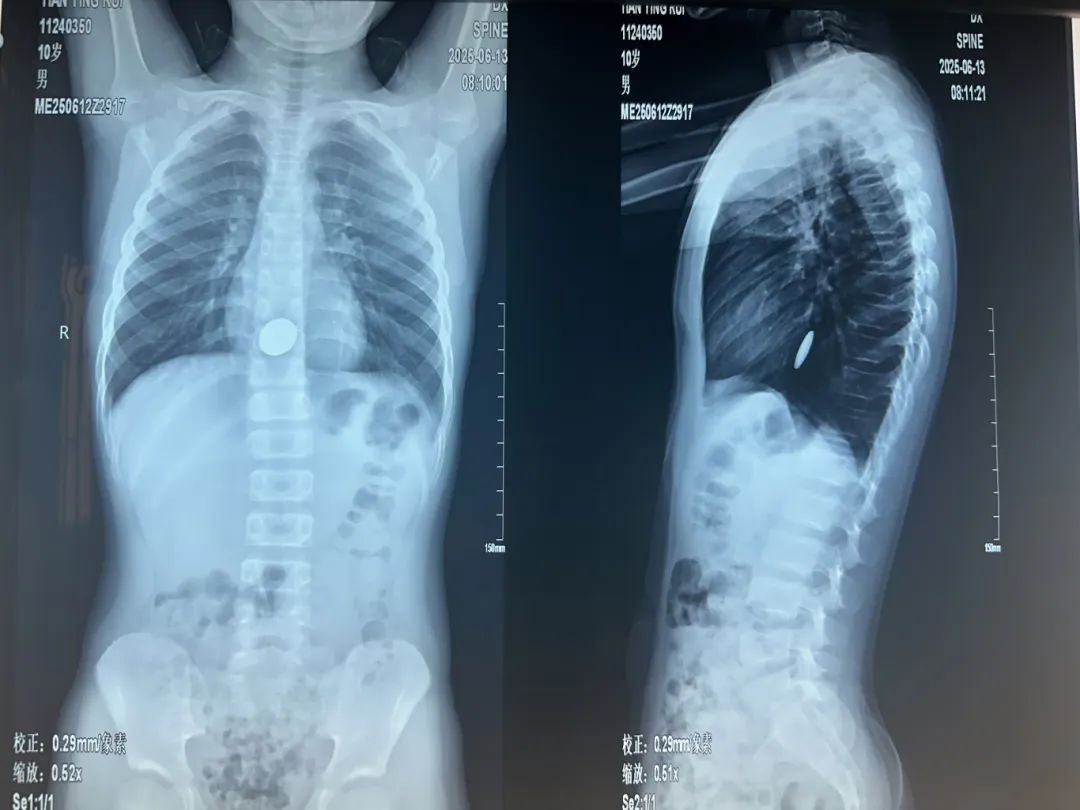

“腹腔镜进去后,发现第一枚磁铁是在升结肠的位置,第二枚磁铁在距离小肠的末端——回肠大概五六十厘米的地方,两枚磁铁紧紧地吸在一起,中间还夹住了一块小肠。”主刀医生普外新生儿外科袁亮主治医师说,取下磁铁后,发现四处肠穿孔,只有将坏死的肠管进行切除后缝合。